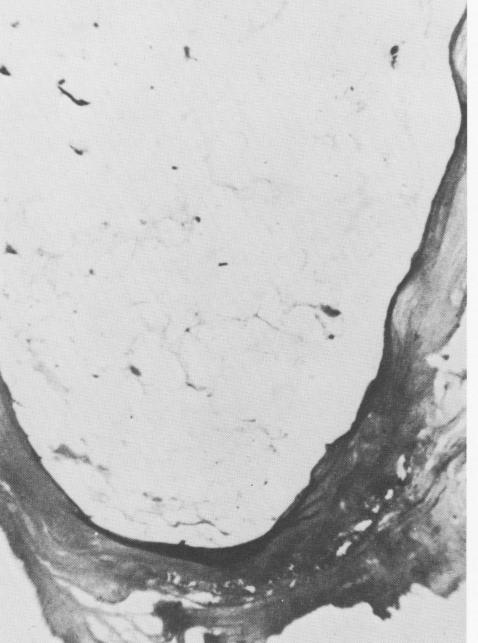

Fig. 4-80 demonstrates that the connective tissues of the "periodontal" membrane extended into the implant material. Under progressively higher snag-

nification these clearly appear to be extensions of the periodontal ligament (Fig. 4-81) .

Fig. 4-80. Even under low power extensions of the connective tissue into the implant are evident. (Courtesy M. I Iodosh. )

2 Extensions of connective tissue into endosseous crystalline implant